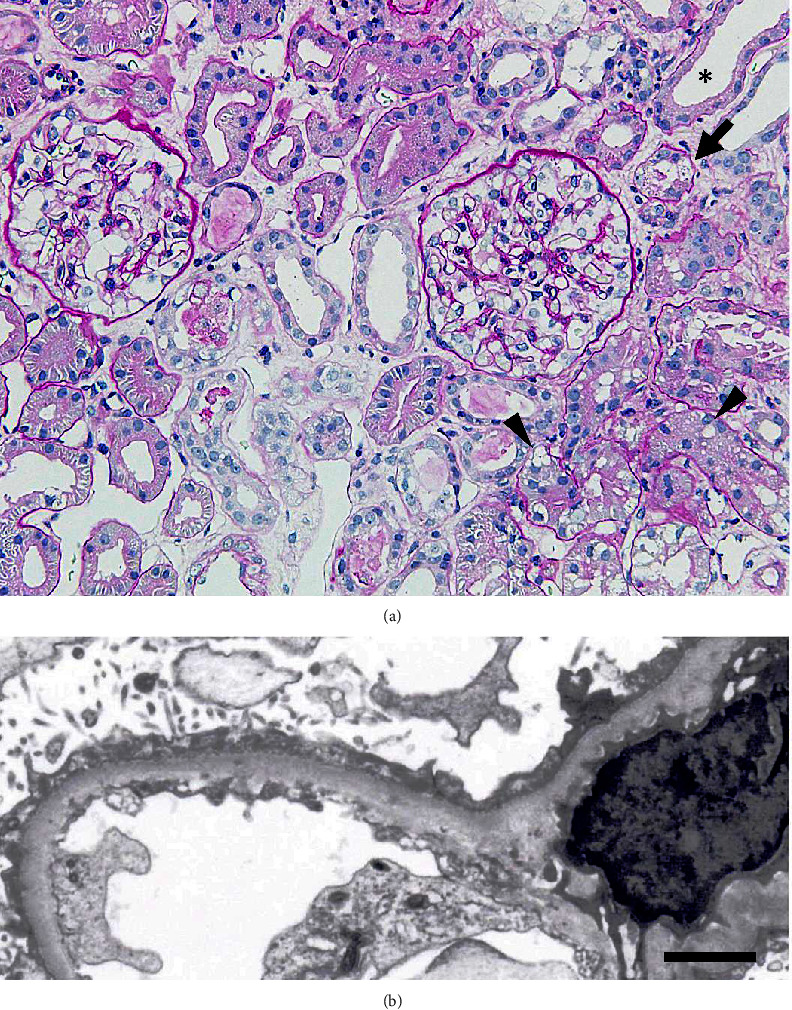

有几种理论可以解释微小病变肾病综合征(MCNS)患者发生严重急性肾损伤(AKI)的原因,但确切的机制仍不清楚。我们遇到过一位经活检证实患有 MCNS 的老年患者,她患有少尿性 AKI,在肾病综合征发病时和首次复发时都需要进行血液透析。在复发期间,我们一直在监测肾小管损伤标志物,即尿N-乙酰-β-D-葡萄糖苷酶和尿α-1-微球蛋白水平。该患者患有高血压。在病情完全缓解 8.5 年后,她的肾病综合征复发并伴有 AKI,需要进行血液透析。经过 7 周的皮质类固醇和环孢素 A 治疗后,血液透析停止。在这次复发期间,我们观察到肾小管损伤标志物和蛋白尿水平突然升高与严重的 AKI 进展之间存在相关性。相反,肾小管损伤标志物和蛋白尿的减少与 AKI 的缓解有关。肾小管损伤标志物和蛋白尿水平的突然升高表明,近端肾小管细胞的蛋白内吞功能可能出现了障碍。此外,肾小球内压急剧下降不太可能是肾小管损伤的主要原因,因为这可能导致肾小球滤过率和蛋白尿水平下降。可以想象,大量蛋白尿加上患者的临床特征,可能会造成肾小管损伤,最终导致该患者出现严重的 AKI。

Several theories have been proposed to explain the development of severe acute kidney injury (AKI) in patients with minimal change nephrotic syndrome (MCNS), but the exact mechanism remains unclear. We encountered an elderly patient with biopsy-proven MCNS who suffered from oliguric AKI, which required hemodialysis at the onset and during the first relapse of nephrotic syndrome. Throughout her relapse, we were able to monitor tubular injury markers, namely, urinary N-acetyl-β-D-glucosaminidase and urinary alpha-1-microglobulin levels. This patient had hypertension. 8.5 years after achieving complete remission, she experienced a relapse of nephrotic syndrome accompanied by AKI, necessitating hemodialysis. The hemodialysis was discontinued after 7 weeks of corticosteroid therapy and cyclosporin A treatment. During this relapse, we observed a correlation between the sudden increase in renal tubular injury markers and proteinuria levels and the progression of severe AKI. Conversely, a reduction in renal tubular injury markers and proteinuria was associated with the resolution of AKI. The abrupt elevation of both tubular injury markers and proteinuria levels suggests a possible breakdown in protein endocytosis in proximal tubular cells. Moreover, it is less likely that the acute reduction in intra-glomerular pressure is the primary cause of tubular injury, as it might result in a decrease in both glomerular filtration rate and proteinuria levels. It is conceivable that massive proteinuria, in conjunction with the patient's clinical characteristics, may contribute to tubular injury, ultimately leading to severe AKI in this patient.